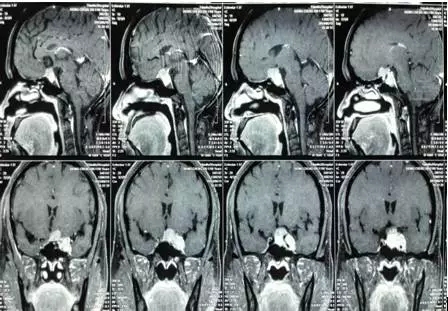

术前MRI片

家住宜宾市珙县的熊某,女,51岁,左眼视力下降3年,两年前因头痛加重到医院检查,被诊断为左侧海绵窦肿瘤。患者及家属辗转多家医院均因肿瘤位置深、手术风险高而被婉拒手术,后慕名到四川医科大学附属第二医院神经外科就诊。

入院后,四川医科大学附属第二医院大外科副主任、神经外科主任顾应江为患者进行了详细的检查,经与患者及家属充分沟通,于8月6日在气管插管全麻下为患者实施左侧海绵窦肿瘤显微切除术,术后病理检查诊断为“脑膜瘤(沙粒体型)”。

“术中发现患者肿瘤位于左侧鞍旁,包绕左侧视神经、颈内动脉等重要结构,手术难度非常大,危险系数也很高,稍有不慎患者很可能会出现视力受损、眼球活动障碍、内分泌紊乱等并发症,甚至危及生命。这次手术很顺利,患者昨天(8月16日)康复出院了。”顾应江主任说道。